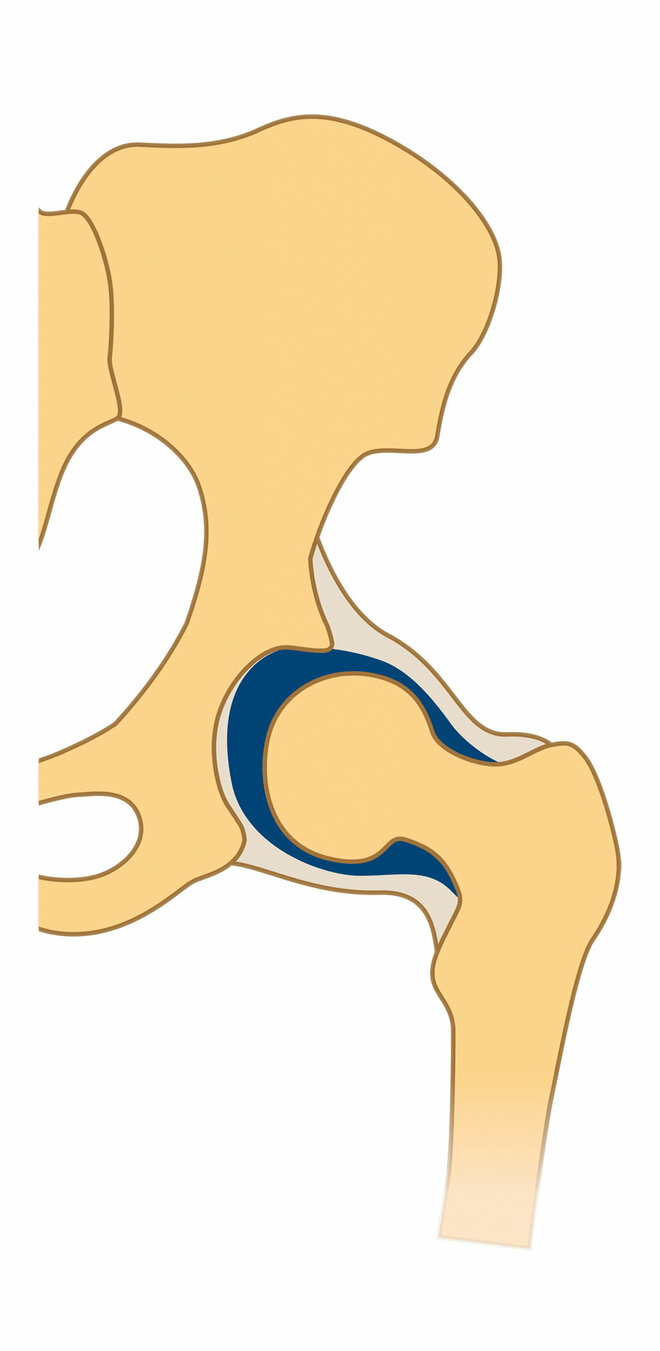

In den meisten Fällen löst sich das Problem in den ersten Lebenswochen von alleine. Bei etwa einem Prozent aber, sagt Ziegler, bleibe eine mehr oder weniger ausgeprägte Fehlstellung und Störung der Knochenreifung bestehen. Und bei maximal einem weiteren Prozent sei sie so stark, dass der Hüftkopf aus der Pfanne zu springen droht oder bereits gesprungen ist (siehe Infografik unten).

Drei Formen der Hüftreifestörung